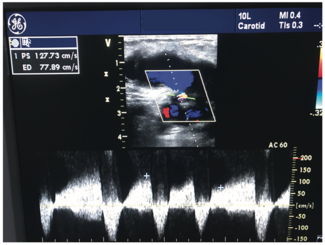

A pseudoaneurysm (PSA) is a false aneurysm that occurs after localized arterial wall injury related to an incomplete hemostatic plug at the injury site.